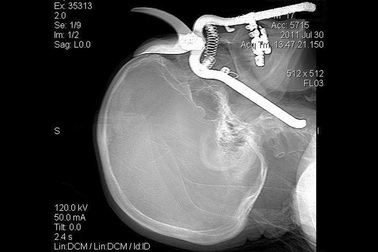

Khó tin những tai nạn dị vật đâm xuyên não vẫn sống sótThật khó tin những nạn nhân này đều sống sót và gần như hồi phục hoàn toàn khi các bức ảnh X-quang cho thấy dị vật nằm rất sâu, thậm chí xuyên qua não.